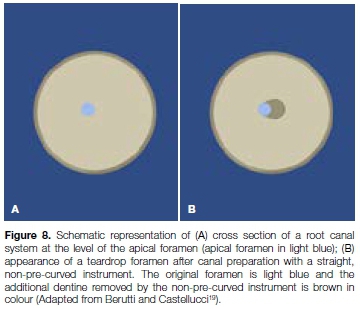

This straightening or transportation can create problems with canal cleaning, obturation and, ultimately, healing.4,5 Apical canal transportation can cause enlargement of the apical foramen (Figures 8a and 8b), which compromises the apical seal.17 Lack of an apical stop might result in extrusion of irrigants and/or obturation materials and cause irritation to the peri-radicular tissues.4,18